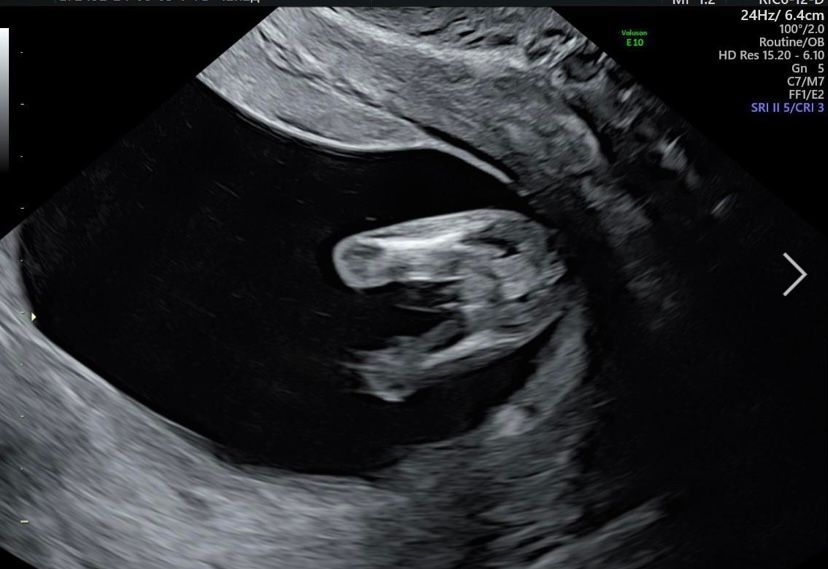

Полина, вот с 1 скрининга фото) мне не понятно было кто, а знающие сразу сказали, что мальчик 😅😅😅 Изображение

Яна, поразительно конечно) у вас вижу мальчика и мошонку и сам краник)

Девочки, как думаете, мальчик, девочка? Девчат погадаем ???